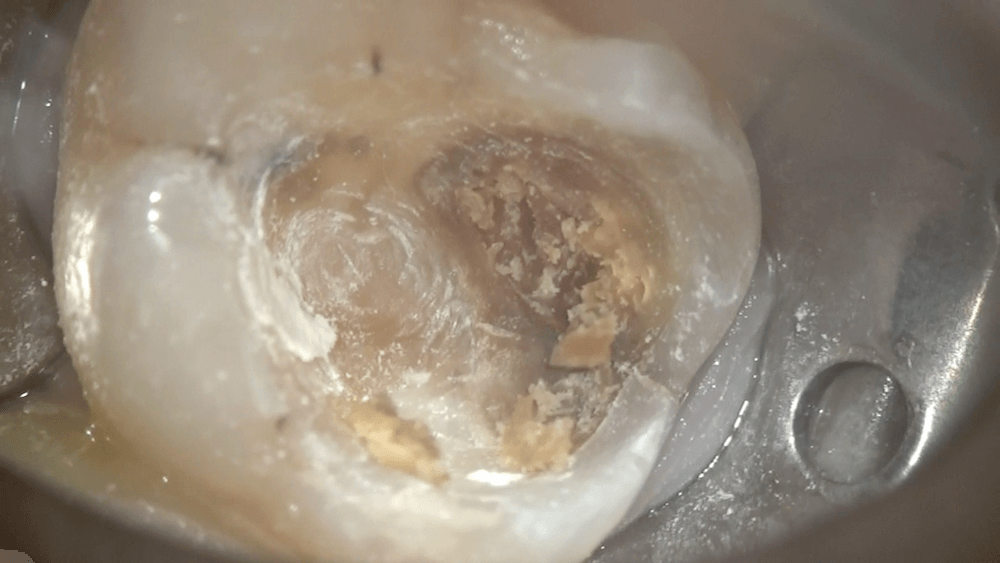

さらに虫歯を取り除き、

虫歯が残っている部分を染め出します。また、ヒビが入っているのがわかりました。